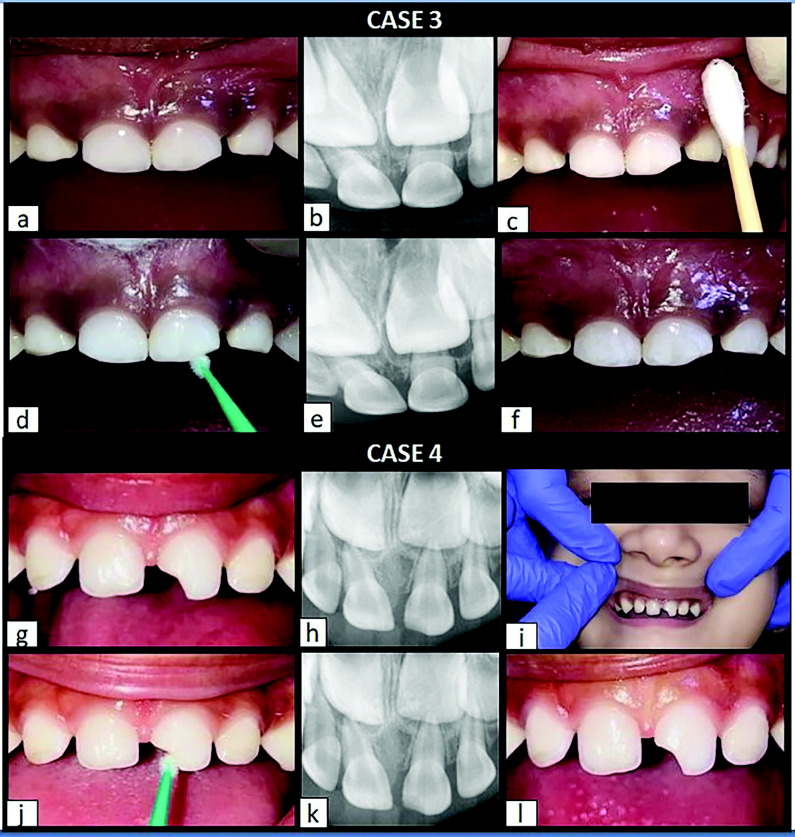

Objective: Dental injury is a significant issue in children due to their immature physical, cognitive, and physiological development. These factors often result in heightened fear and behavioral challenges during their first visit following trauma, which can compromise the quality of treatment and lead to a poor prognosis for the affected tooth. Silver Diamine Fluoride (SDF), a colorless solution approved by the US FDA for treating dental hypersensitivity and caries, offers a simple, painless, and non-invasive treatment option. Its application involves a paint-on technique with a powerful fluoride formulation, making it an ideal choice for the initial management of enamel and dentin fractures in primary teeth, particularly in uncooperative young children.

Case description: This case series described four cases in which SDF was successfully used as the primary treatment for Ellis Class IX anterior tooth trauma in very young children with negative behavior responses in the dental setting. The procedure required minimal armamentarium and was well-tolerated by all patients.

Conclusion: In each case, the use of SDF yielded successful and satisfactory outcomes, with a favorable prognosis for the affected teeth. Additionally, the treatment contributed to a positive shift in the children's attitudes toward dental care.